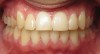

Mouth breathing has also been associated with dental malocclusions in children.2 Zicari and colleagues' analysis of 71, 6- to 12-year-old mouth breathing children revealed a 72.5% incidence of reduced transverse diameter of the maxilla and increased vertical dimension, a 32.5% incidence of cross bite, a 43.7% incidence of skeletal class II malocclusions, and a 90% incidence of atypical swallowing patterns. The results showed a strong correlation between oral breathing and malocclusions, which manifests as both dentoskeletal and functional alterations, leading to a dysfunctional malocclusive pattern (Figure 1 through Figure 3). The study concludes that “this dysfunctional malocclusive pattern makes it clear that the association between oral breathing and dental malocclusions represents a self-perpetuating vicious circle in which it is difficult to establish if the primary alteration is respiratory or maxillofacial. Regardless, the problem needs to be addressed and solved through the close interaction of the pediatrician, otorhinolaryngologist, allergologist, and orthodontist.”

(1.) In children, mouth breathing with low tongue posture can result in narrow maxillary arches, dental crowding, tongue scalloping, and anterior open bites. Images courtesy of Kevin Boyd, DDS, MSc.

Figure 1